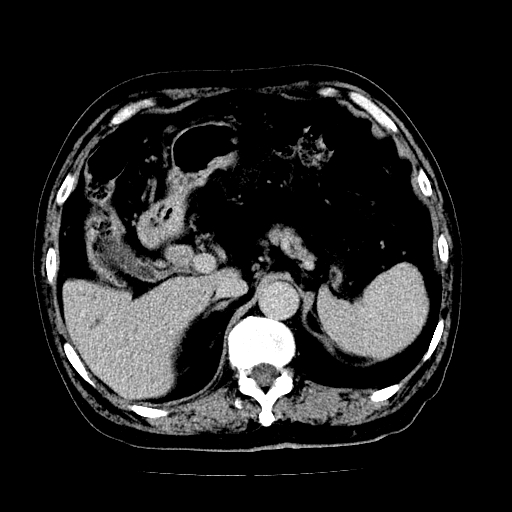

男,71岁,皮肤黄染四天。

肝内外胆管及胆总管上段扩张,考虑为梗阻所致,建议mrcp检查。

考虑胆总管癌并肝内外胆管扩张。

支持考虑胆总管癌并肝内外胆管扩张。 局部应薄扫。心包钙化。

胰腺上端胆总管内见软组织影,强化不明显,结合临床,还是考虑低位梗阻性黄疸,胆总管癌可能性大